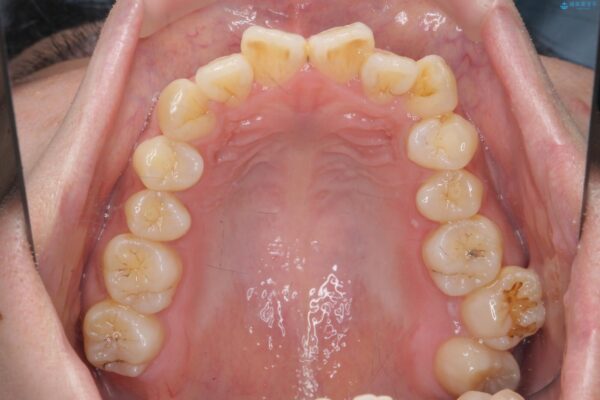

治療を終えて

患者様の協力度も高く、リファインメントなしで治療を終えることができました。

抜歯をしない場合、多くは歯と歯の間を少し削ることでスペースを作ります。

動的治療期間は約4か月となり、短い治療期間で前歯のガタつきが改善され大変喜んでいただけました。

治療後

気になる犬歯のガタつきをマウスピース矯正で改善 治療後画像 気になる犬歯のガタつきをマウスピース矯正で改善 治療後画像 気になる犬歯のガタつきをマウスピース矯正で改善 治療後画像 気になる犬歯のガタつきをマウスピース矯正で改善 治療後画像